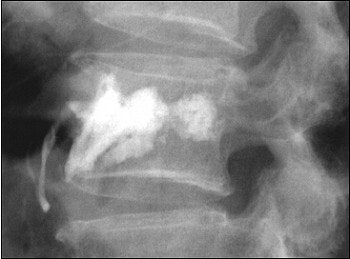

![]() |

| Final result of a vertebroplasty procedure on a lateral radiograph. Image courtesy of Dr. John Mathis. |